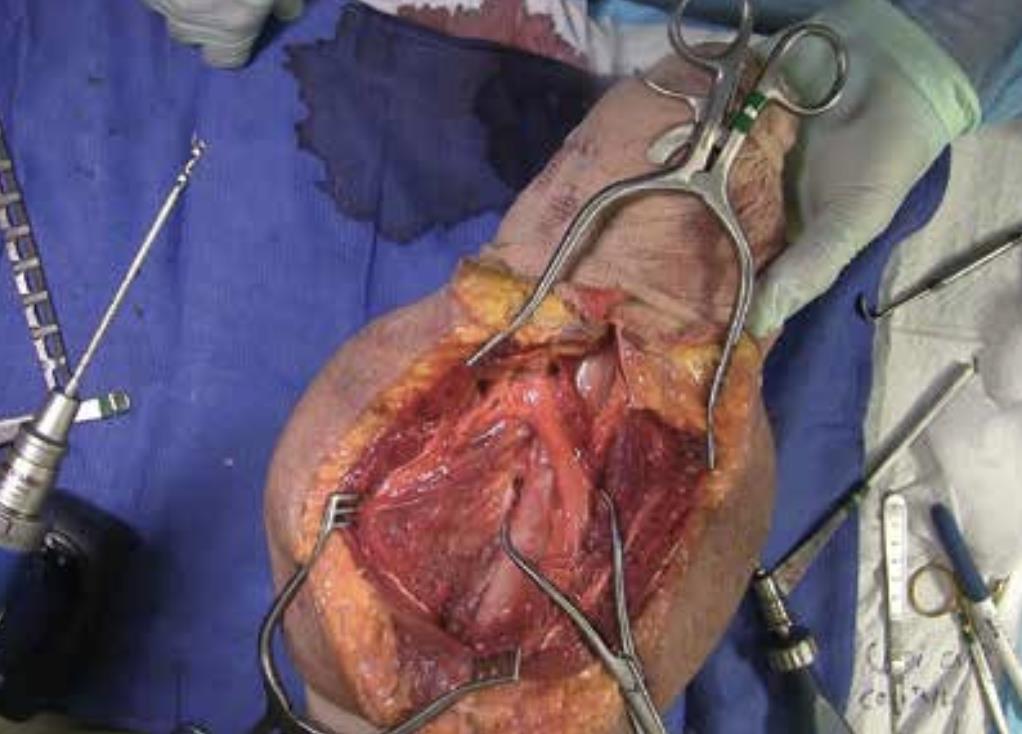

• Exposure

• Expose the humerus using the optimal approach for the fracture location.

• Reduce Fracture

• Debride and reduce the fracture.

• Address fracture pattern using lag screws as needed.

• Bone clamps are useful for provisional fixation.